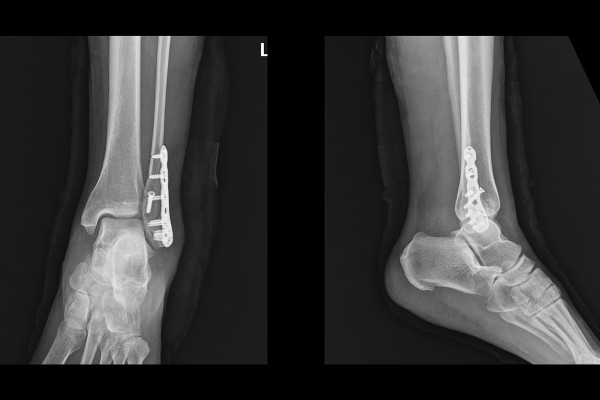

환자분께서 빠른 회복과 후유증이 없기 위한 수술적 치료를 받고자 내원하셨기에, 현재 환자분 발목 상태와 수술 내용을 설명드리고서 좌측 발목 골절 정복술 및 금속판 고정술(Lt. ankle ORIF with plate for lat. malleolar Fx.)을 진행하였습니다.

내원 다음날 바로 수술을 진행하였고, 실시간 X-RAY인 C-ARM을 이용하여 확인하면서 골절선을 가로지르는 지연나사(lag screw)와 금속판(plate)으로 강하게 고정해줍니다.

수술 후 X-RAY를 확인해보면 잘 고정된 발목이 확인됩니다.